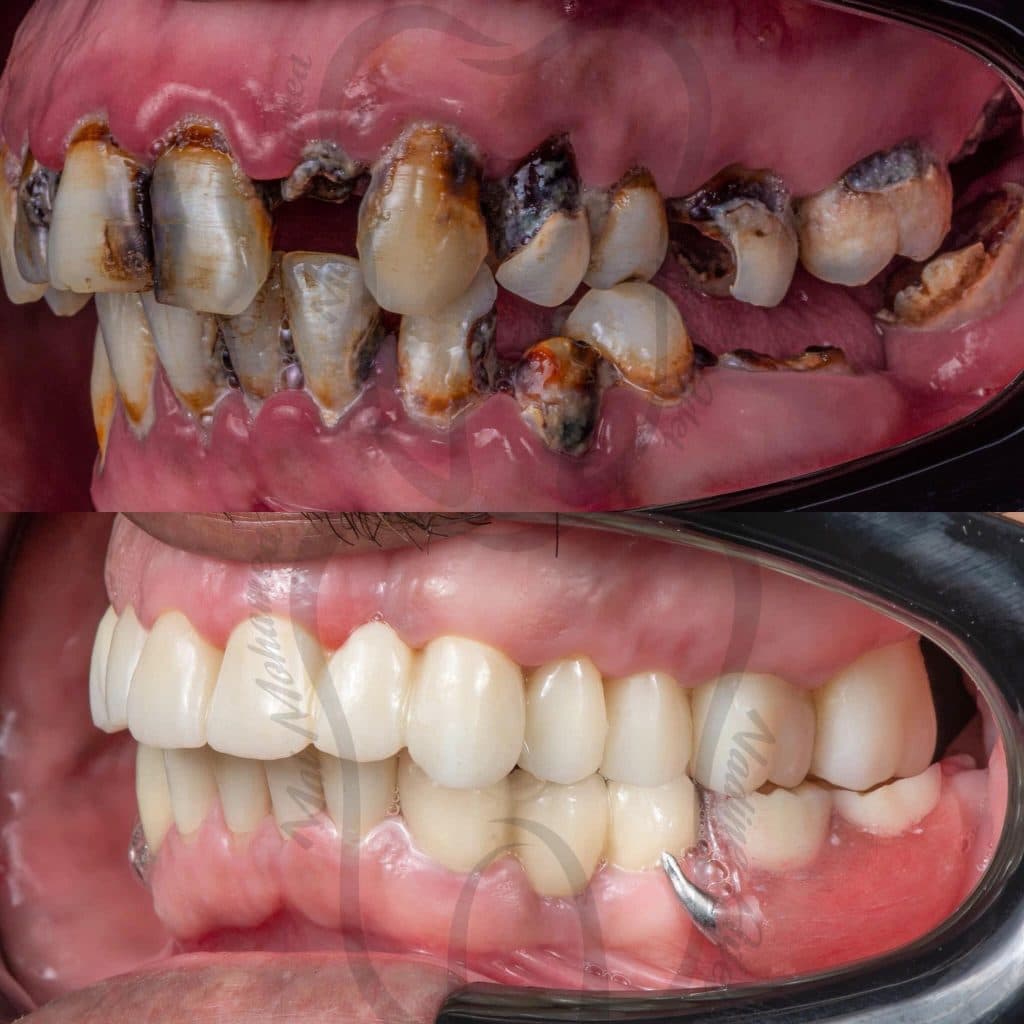

Graduation Case 🎓🎓

5th year student, PUA, Egypt

This case has been done together with my partner Dr Mai Marzouk

Our treatment plan included:

📌 10 Extractions

📌Full Mouth scaling and Root planing

📌 12 Endodontic treatment

📌 6 Post and Core

📌 Full Mouth Composite Restoration

📌 20 Unit Zirconium

📌 5 Unit PFM

📌 Lower Arch Class I Metallic RPD